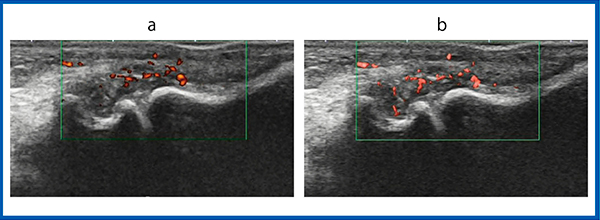

症例3〜5は,SMI画像で血流信号が検出され,パワードプラ画像では血流信号が見られなかったものである。症例3は,左肘頭窩の滑膜炎で,SMI画像では豊富な血流信号が得られているが,パワードプラ画像ではほとんど血流信号が検出できていない(図4)。また,症例4は左手関節橈側の滑膜炎であるが,パワードプラ画像では血流信号を描出できていないが,SMI画像は高い感度で血流をとらえている(図5)。症例5は,左膝外側の滑膜炎であるが,これもパワードプラで検出されない血流信号が,SMI画像では豊富に得られている(図6)。

図4 症例3:左肘頭窩の滑膜炎

a:パワードプラ画像 b:SMI画像

図5 症例4:左手関節橈側の滑膜炎